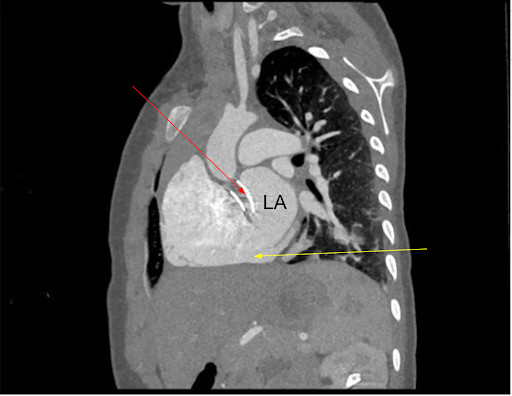

Varicella Fetal Myocarditis – A Rare Finding in the Current Era of Universal Immunization in our April 2026 Issue. North American Editions - mailchi.mp/25e705722970/a…. International Edition - mailchi.mp/b3ca4160d15d/c…